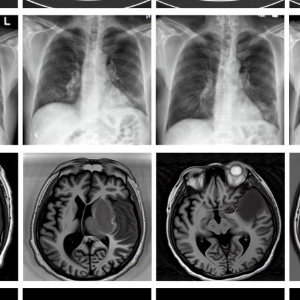

图为由MINIM生成的高质量医学合成图像(受访者供图)

“目前公开的医学影像数据非常有限,我们建立的生成式模型有望解决训练数据不够的问题。”北京大学未来技术学院助理研究员王劲卓说,研究团队利用多种器官在CT、X光、磁共振等不同成像方式下的高质量影像文本配对数据进行训练,最终生成海量的医学合成影像,其在图像特征、细节呈现等多方面都与真实医学图像高度一致。

实验结果显示,MINIM生成的合成数据在医生主观评测指标和多项客观检验标准方面达国际领先水平,在临床应用中具有重要参考价值。在真实数据基础上,使用20倍合成数据在眼科、胸科、脑科和乳腺科的多个医学任务准确率平均可提升12%至17%。